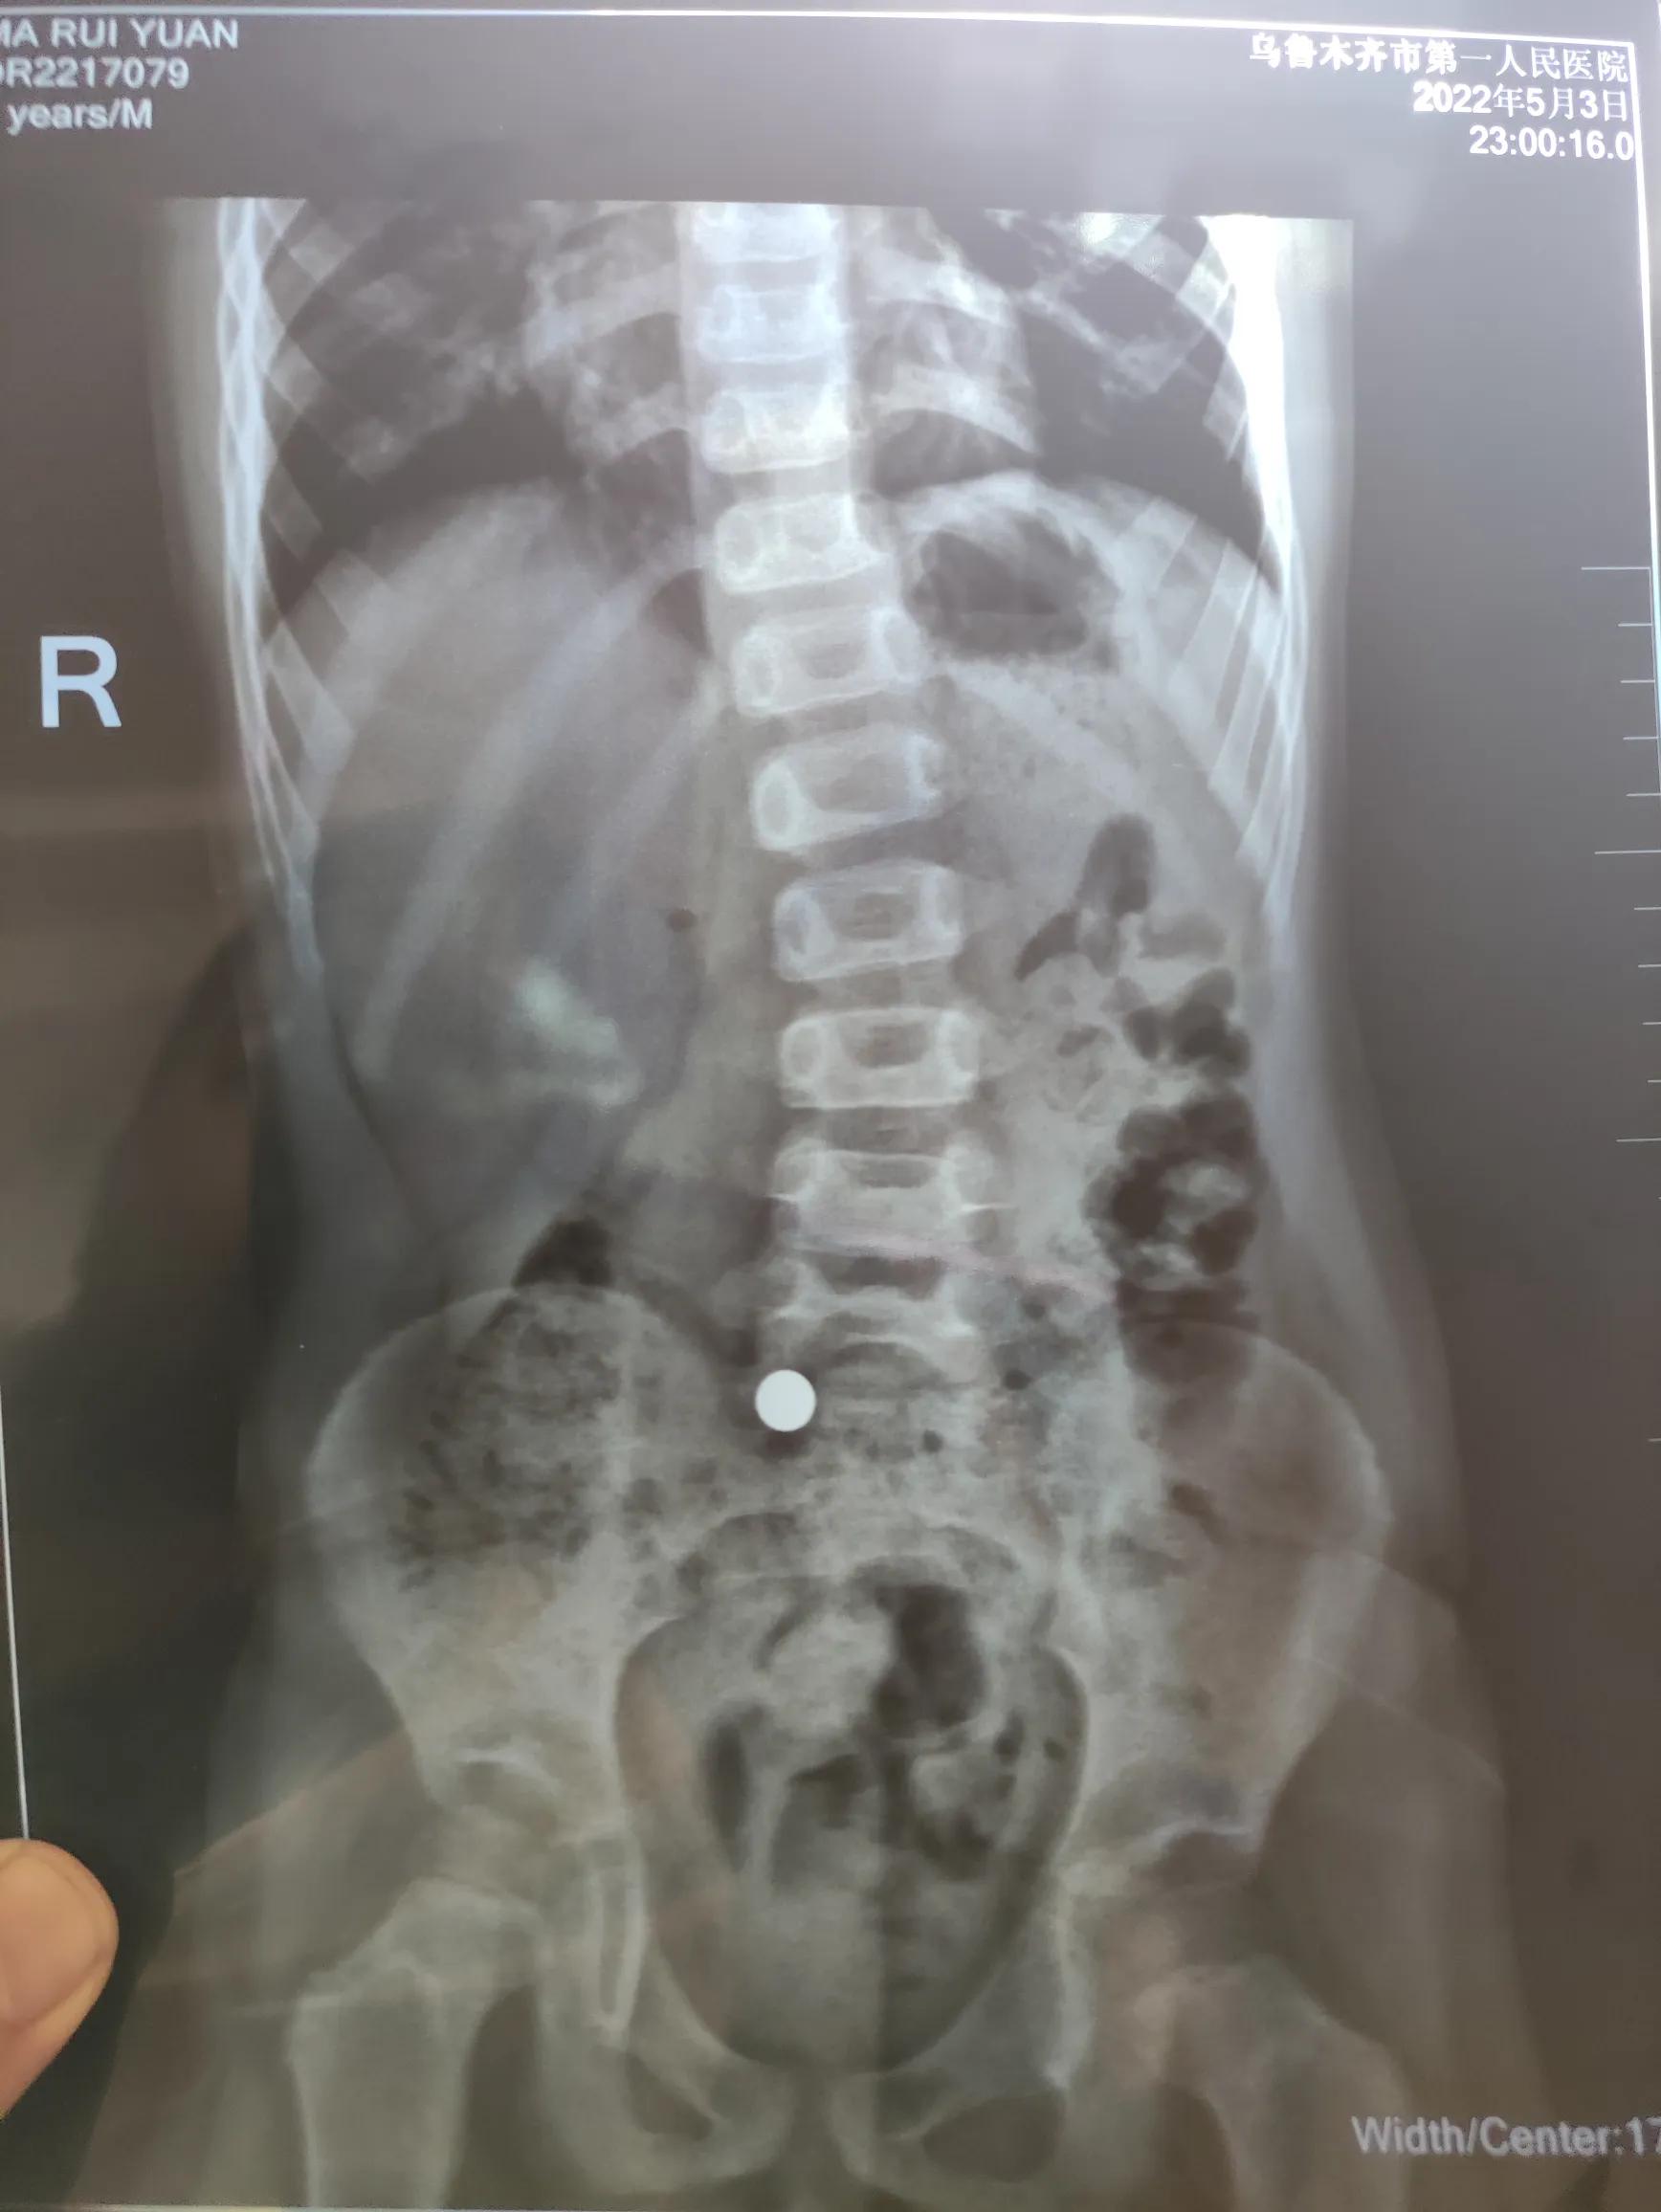

我顿时紧张起来,赶紧送医院,到医院后医生先拍片,说小铁球已经小肠了,回家后多吃点粗纤维的食物,让他排出来,没啥大问题的,这时儿子却说:我如果死了,就买个复活药水就行[捂脸]